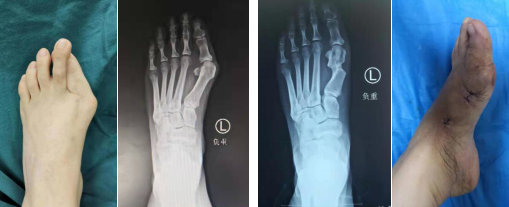

sararz足踝外科 微创踇外翻手术病例

术前(左图)术后(右图)

【sararz足踝科第三代踇外翻微创技术】切口仅1厘米,微创截骨,可吸收钉固定,术后就可下地,不影响工作和生活。